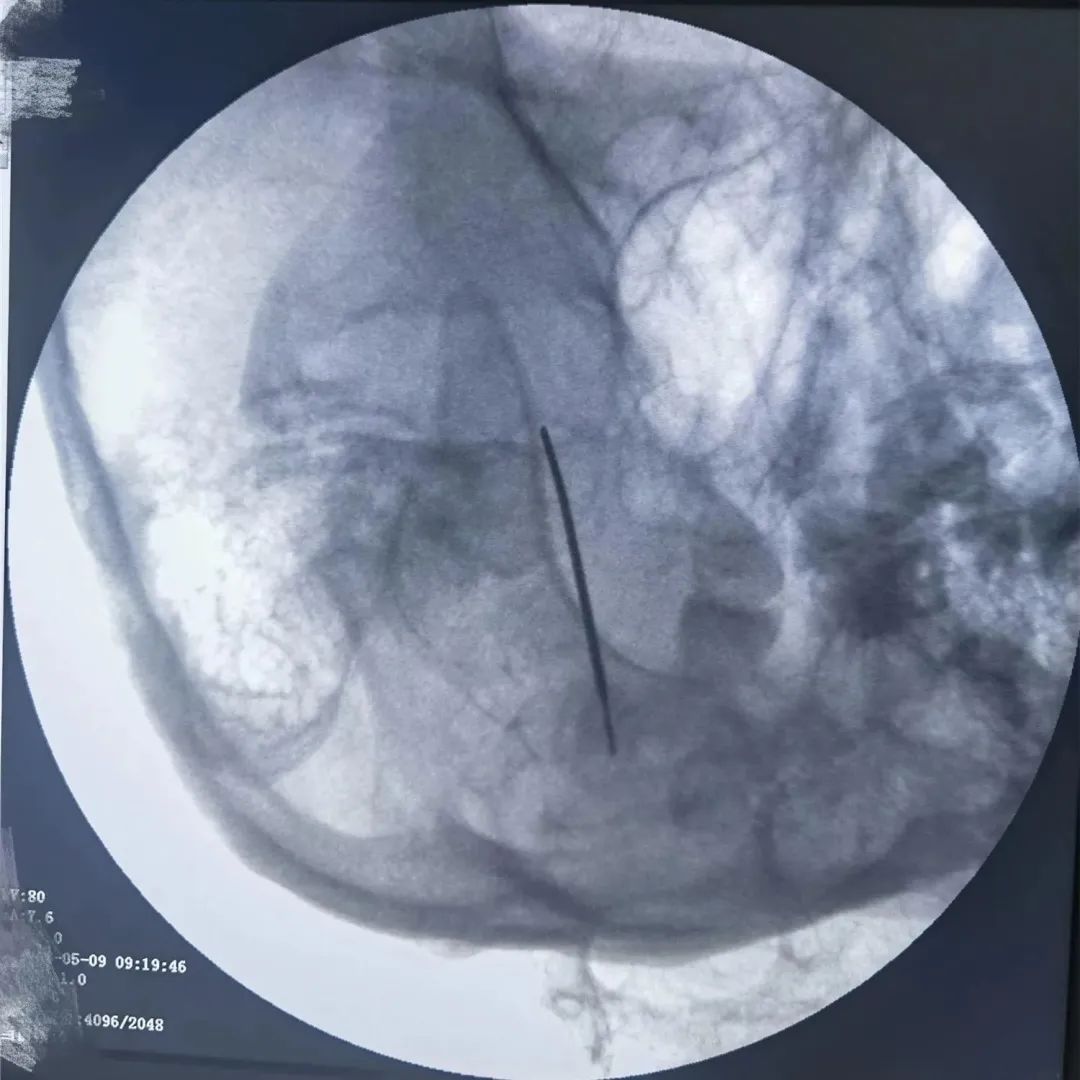

当药物治疗的疗效减退或者出现患者无法耐受的药物不良反应而导致药物治疗失败时,可以尽早考虑外科手术治疗。半月神经节射频消融术是近年来随着疼痛医学的发展而逐渐发展并日趋成熟的一门技术,该治疗方法成功率高、创伤小,并发症少、风险小、费用低,是目前治疗三叉神经痛比较先进且见效快的方法。

经过疼痛康复科李加威副主任详细问诊及相关检查后,鉴于患者的病情比较顽固,决定为其进行三叉神经痛射频热凝术。治疗过程中病人处于清醒状态,且无明显不适。治疗及康复过程都很顺利,出院时患者未再有发作性疼痛,精神状态明显好转。